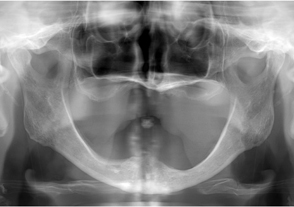

- 治療前のレントゲン